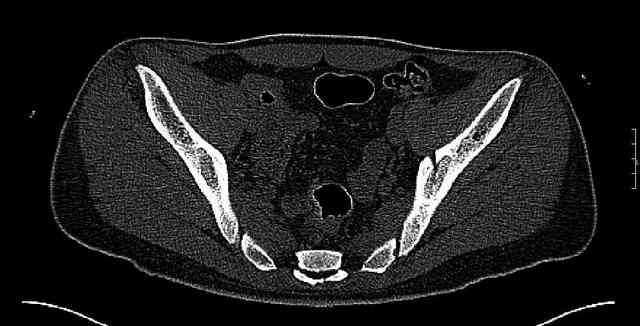

Some more images. Does it help to guess which part of the acetabulum is displaced?

Normal appearing SI joints and a healed posterior column limb... my bet's on caudal segment displacement.